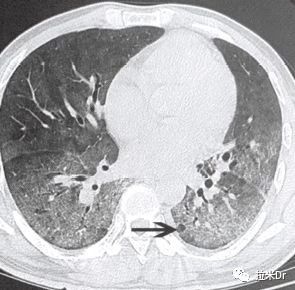

3、肺孢子菌肺炎(PCP)

PCP是由耶氏肺孢子菌引起的肺部感染性疾病,在艾滋病患者中极为常见,也是患者死亡的主要原因。在首次确诊的艾滋病患者中,PCP发生率为70~80%,病死率高达20~40%。90%的PCP发生在CD4+T细胞计数<200个/μl的患者中。典型表现包括:

发热

干咳

进行性呼吸困难

低氧血症